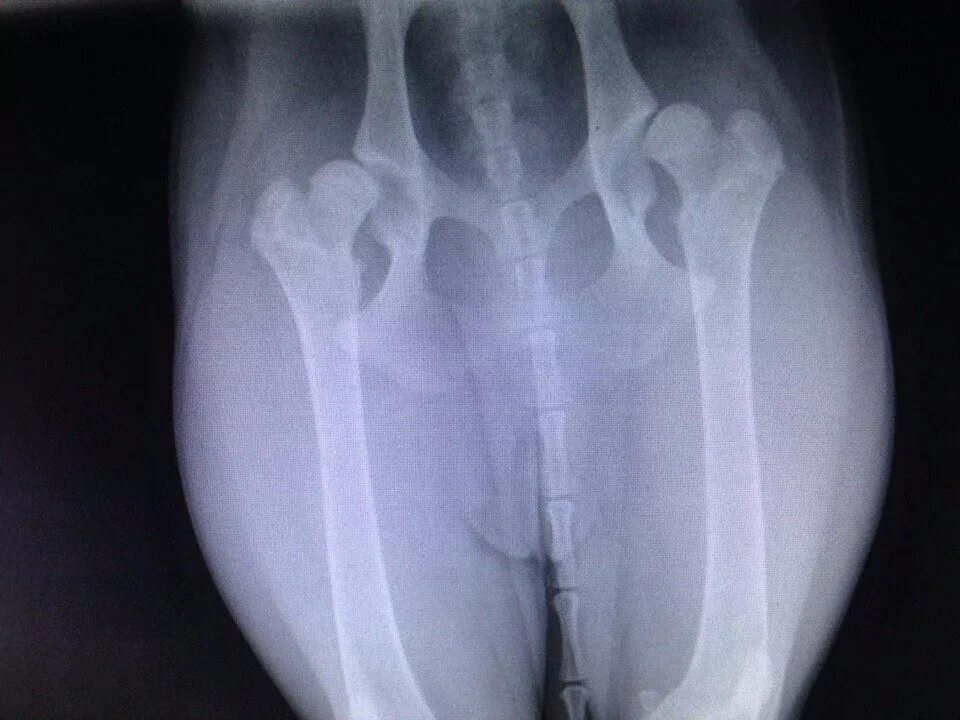

Операция при дисплазии